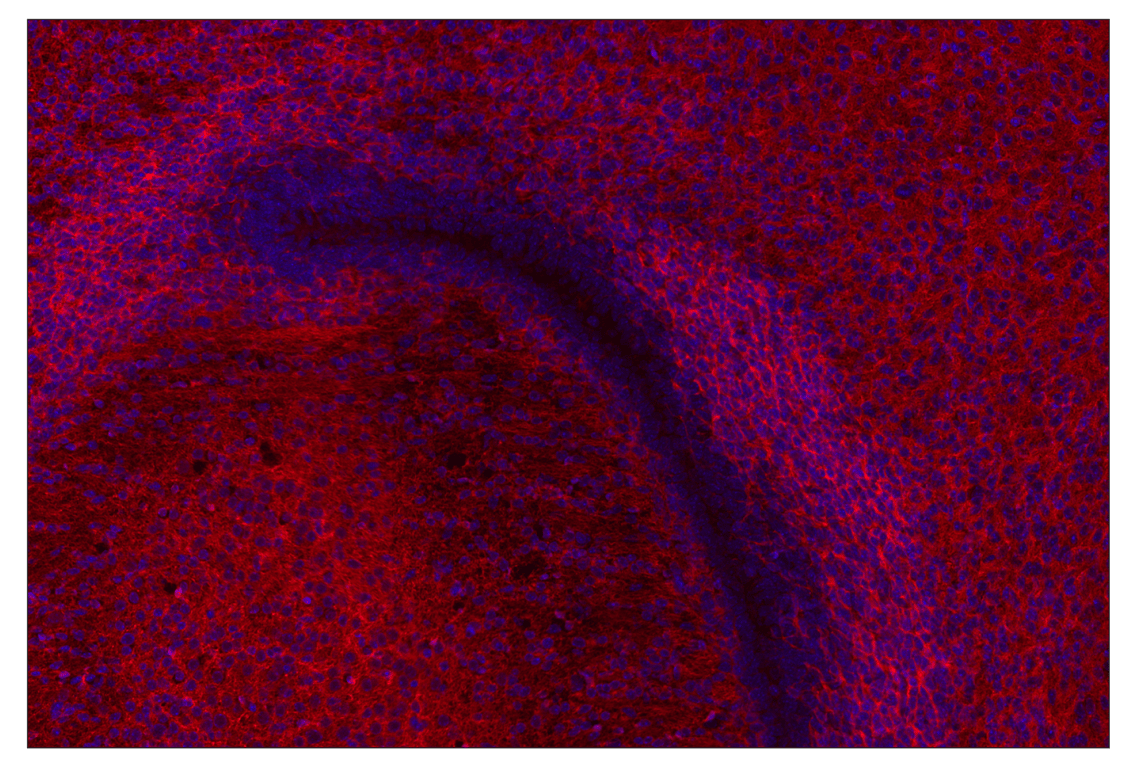

Doublecortin (E3S7L) Rabbit Monoclonal Antibody (Alexa Fluor® 555 Conjugate) #40317

Immunohistochemistry (Paraffin) 1:50 - 1:200

Doublecortin (E3S7L) Rabbit Monoclonal Antibody (Alexa Fluor® 555 Conjugate) recognizes endogenous levels of total doublecortin protein. Species reactivity for IHC-P is mouse and rat only.